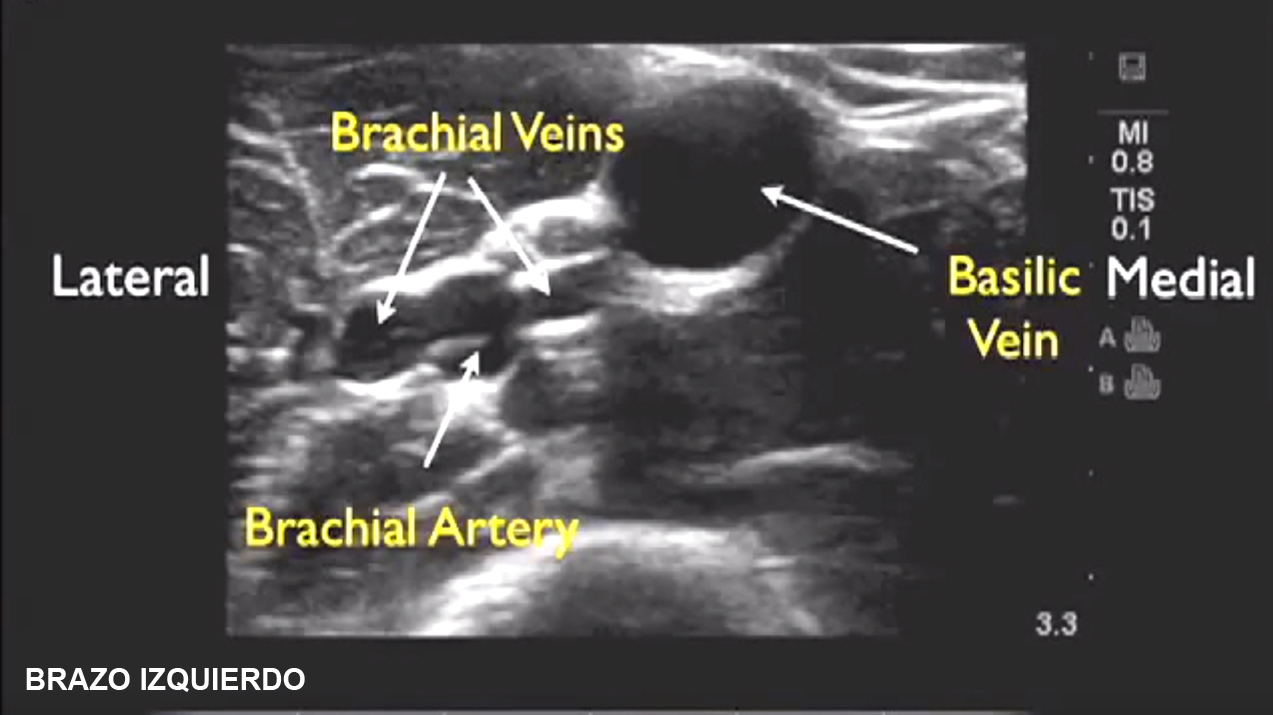

Canalización de vías venosas periféricas guiada por ecografía Basilica Y Cefalica Un buen funcionamiento de las venas cefálica y basílica es crucial para mantener una adecuada circulación periférica en el miembro superior. La vena cefálica drena la porción lateral (radial) de la mano, el antebrazo y el brazo, comunicándose a lo largo de su recorrido con la vena basílica, la cual drena el aspecto ulnar (medial). En este artículo discutimos la. Basilica Y Cefalica.

Canalización de vías venosas periféricas guiada por ecografía Basilica Y Cefalica La vena cefálica nace, junto con la vena basílica, del arco venoso dorsal y también se hace anterior (vena cefálica del antebrazo). La vena basílica discurre por el lado ulnar del brazo y contribuye en el drenaje de la red venosa dorsal de la mano. Un buen funcionamiento de las venas cefálica y basílica es crucial para mantener una adecuada. Basilica Y Cefalica.